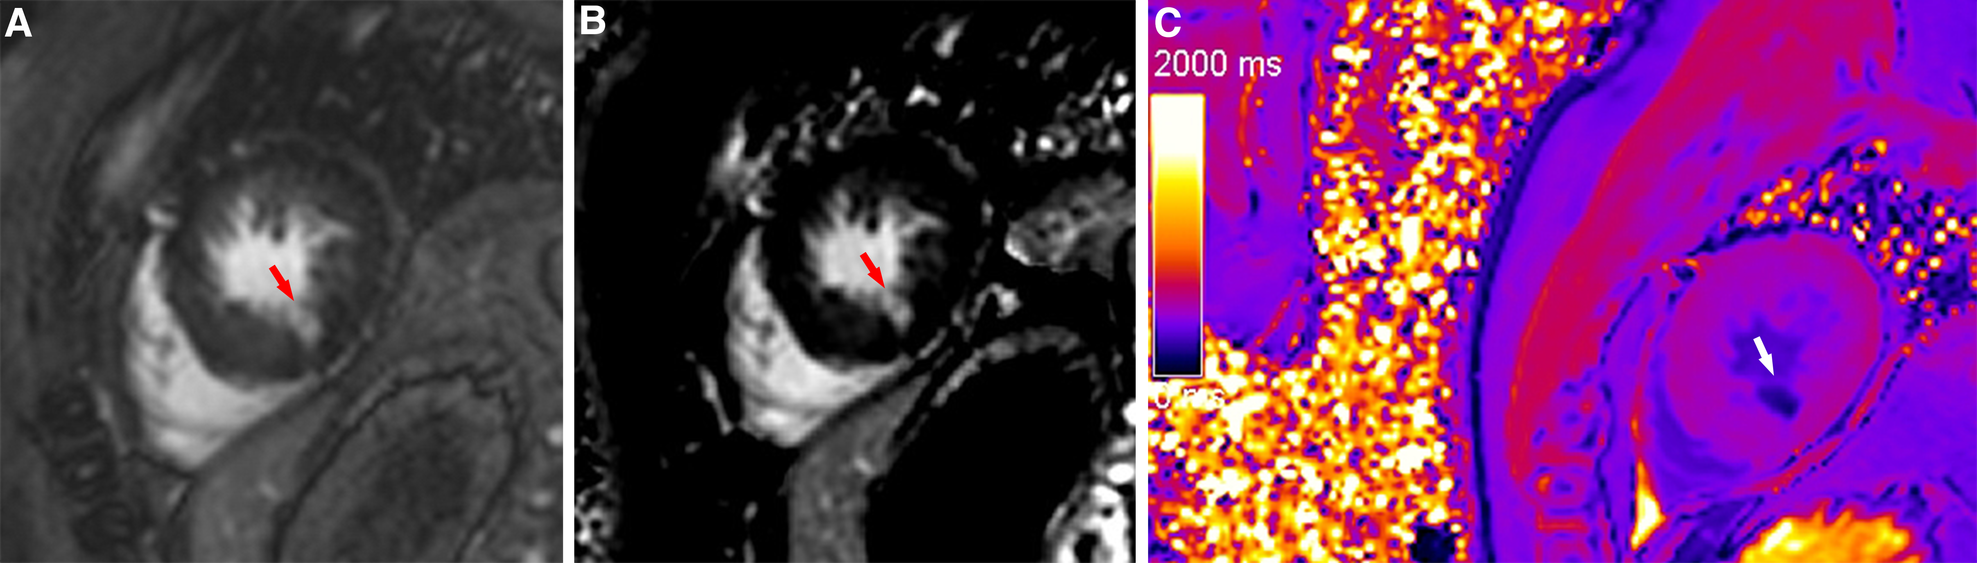

Figure 4

A typical case in which post-contrast T1 mapping reduced the number of uncertain infarcted segments. An ambiguous focal scar (red arrow) could be observed on magnitude (A) and PSIR (B) in the inferior subendocardium of the apex, but the observer's diagnostic confidence was low. The observer's diagnostic confidence in the scar (white arrow) was improved on post-contrast T1 mapping (C); thus, the affected segment was classified as an infarcted segment.